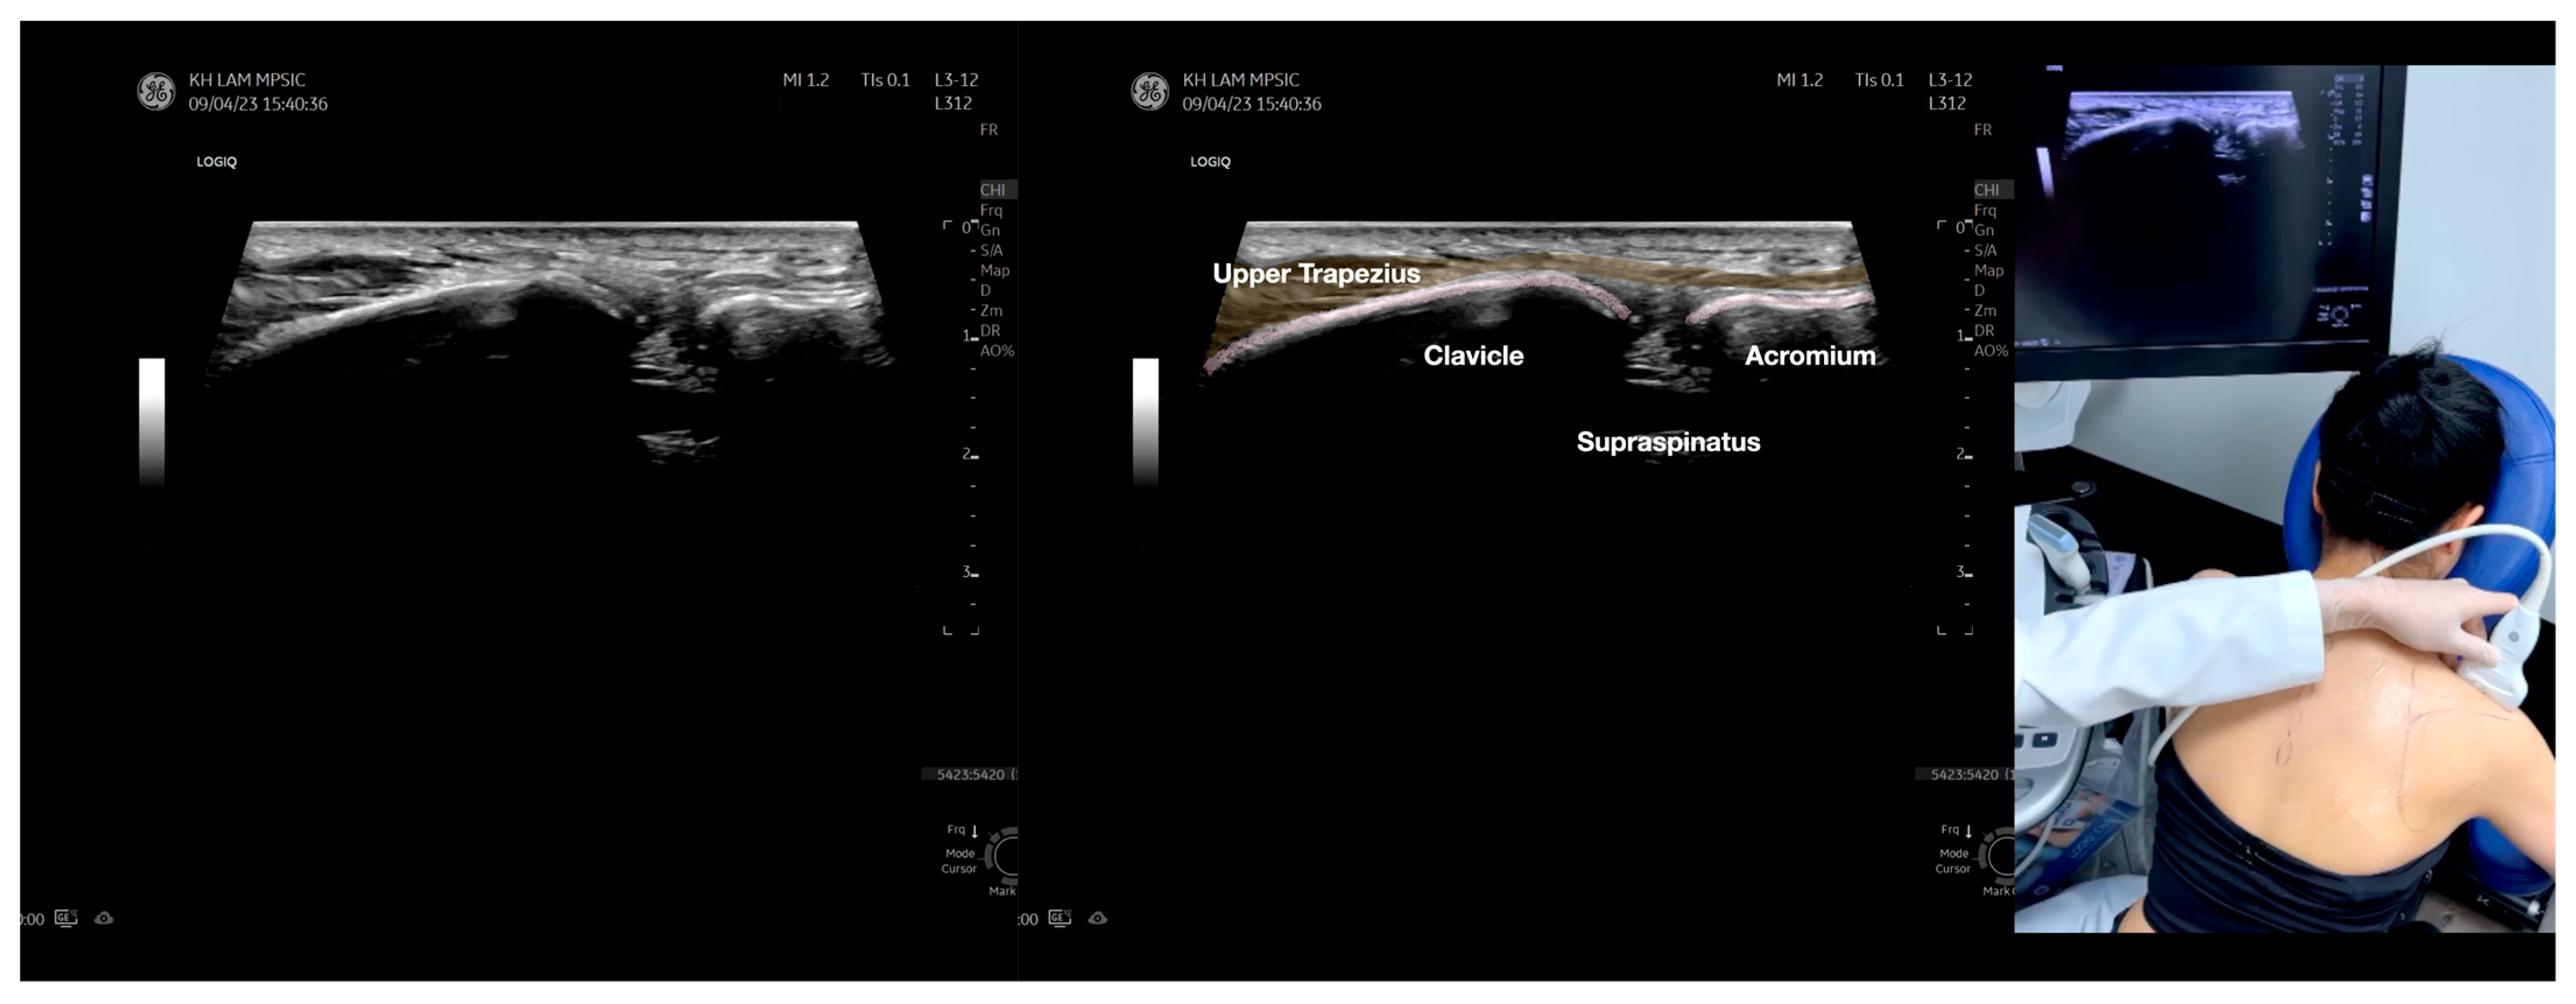

Figure 5.

Sonoanatomy of scanning the infraspinatus fascia in the sagittal plane from the rhomboid minor laterally, then back to the rhomboid major. The step-by-step scanning techniques of the structures illustrated in this figure have been shown in Video S9. Available online: https://www.dropbox.com/s/gu9hhrdq9erin6n/Figure%205.docx?dl=0 (accessed on 1 January 2023).